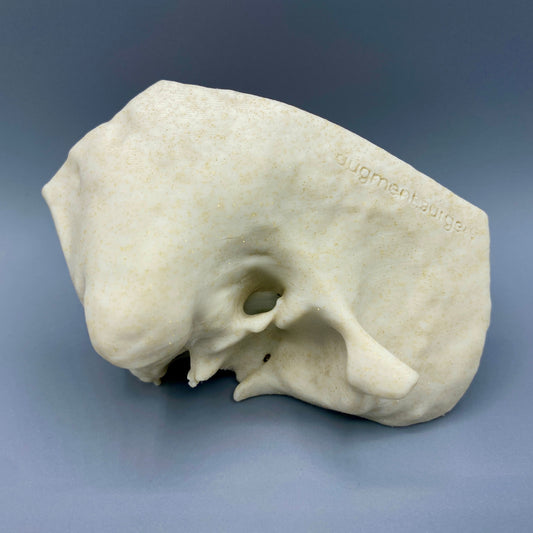

Plant-based surgical simulators made in the U.S.A.

Dissect each one to learn human temporal bone anatomy, hearing and vestibular systems.

Delta-Left OpenEar 3D Temporal Bones

Regular price $74.00 USDRegular priceUnit price per -

Delta-Right OpenEar 3D Temporal Bones

Regular price $74.00 USDRegular priceUnit price per -